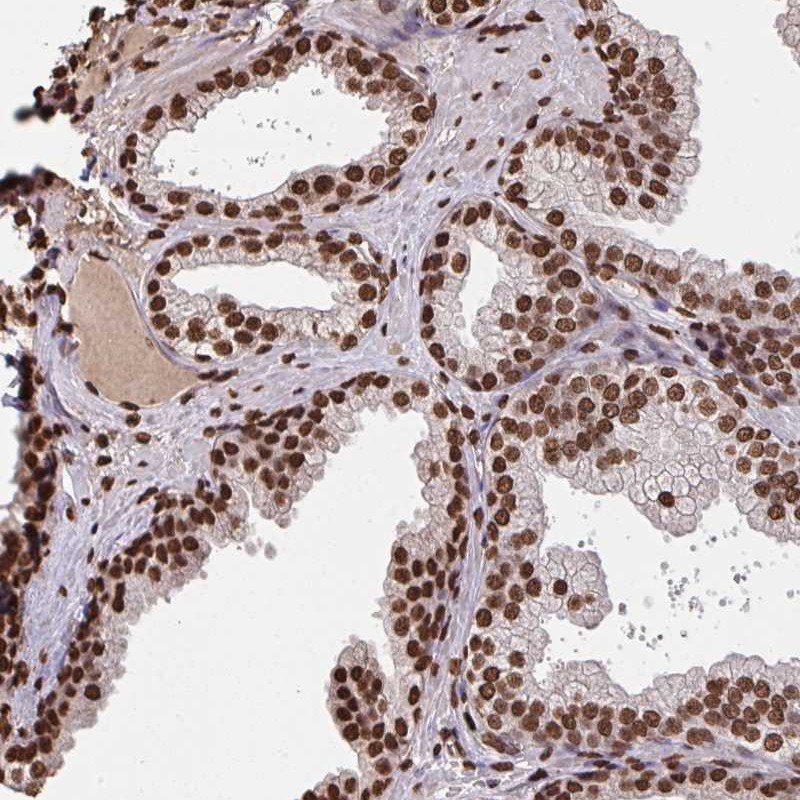

Immunohistochemical staining of human prostate shows strong nuclear positivity in glandular cells.